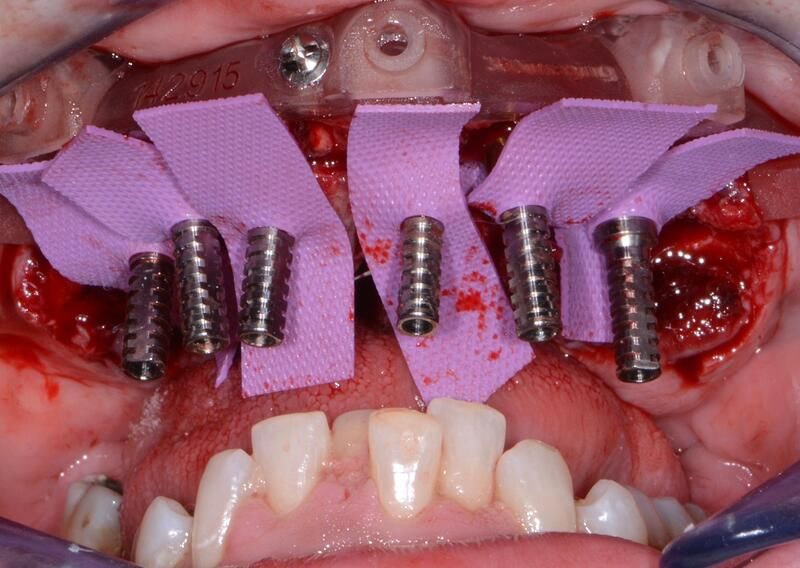

全口組合式導(dǎo)板病例

術(shù)中過(guò)程